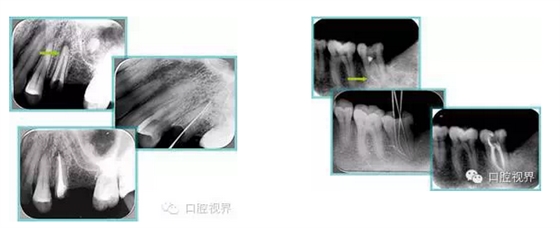

左圖和上圖為干髓治療后牙齒,齲齒疏通后進行根管充填。

如圖為塑化加根充處理后牙齒 X 線片。

常見有修復性鈣化和增齡性鈣化。下面為根管鈣化 X 線片。

右圖及下圖為器械折斷的 X 線片。箭頭處示折斷器械。